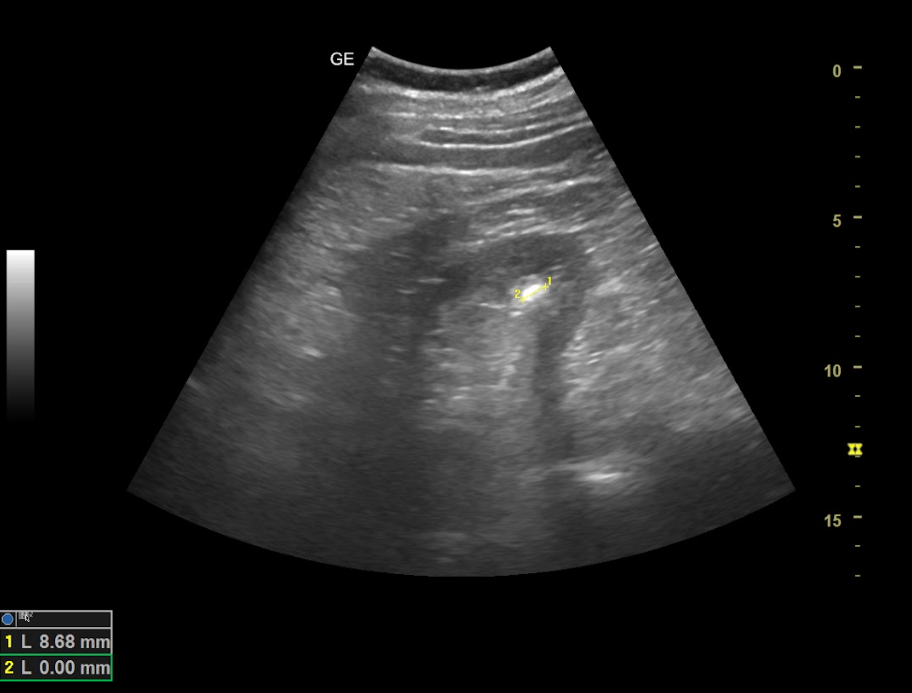

Hallazgos ecográficos

Ambos riñones son de tamaño similar considerándose normales y no apreciando hidronefrosis asociada. En el interior del riñón derecho se aprecia litiasis renal única que proyecta sombra posterior de diámetro máximo de 8,68 mm y potencial responsable del cuadro.